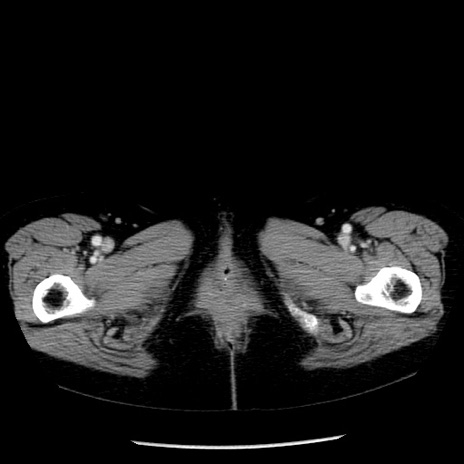

症例13(横断像)

【症例】70歳代女性

【主訴】腹痛、嘔吐

【現病歴】15時間程前(昨晩)より腹痛あり。今朝になっても症状の改善なく、嘔吐あり。腹痛も増悪あり、救急外来受診。

【既往歴】子宮癌全摘術後

【身体所見】意識清明、BP 121/72mmHg、P 74bpm、SpO2 100%(RA)、腹部:平坦・軟、腸雑音ほぼ聴取せず。下腹部・心窩部・臍左上に圧痛あり。反跳痛なし。

【データ】WBC 10600、CRP 0.15